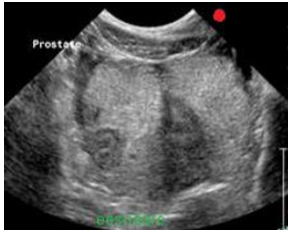

Prostate biopsy technique.

FNA or TCB:

Transabdominal:

cyst or abscess aspiration (empty completely or it may leak), solid lesion

Trans-rectal technique possible